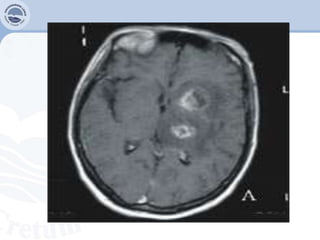

Toxoplasmose (T. Gondii)

 Resulta de reactivação parasitaria anterior.

 CD4<200cel/mm³+ ausência de profilaxia

Diagnóstico

 Clínico: confusão mental, convulsões, hemiplegia e hemiparesia.

80% esta localizada, e 20% encefálica.

 Imagilogico: TAC e RMN

 Sorológico: IgG anti-toxoplasmose no sangue e LCR.